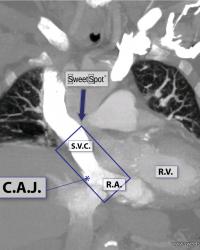

Figure - 04

Enhanced coronal CT reconstruction |